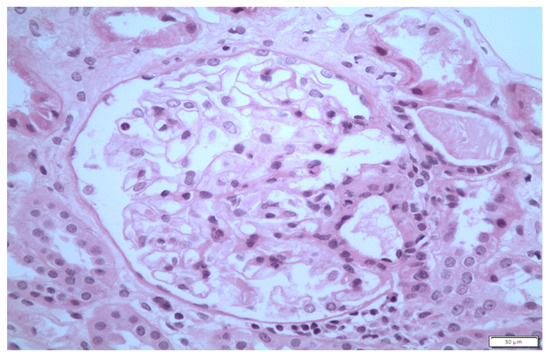

2. Case 1 Description: MCD Associated with Tamoxifen

3. Case 2 Description: MCD Associated with D-Penicillamine

4. Case 3 Description: D-Penicillamine-Associated MCD

5. Case 4 Description: Pembrolizumab-Axitinib-Induced MCD